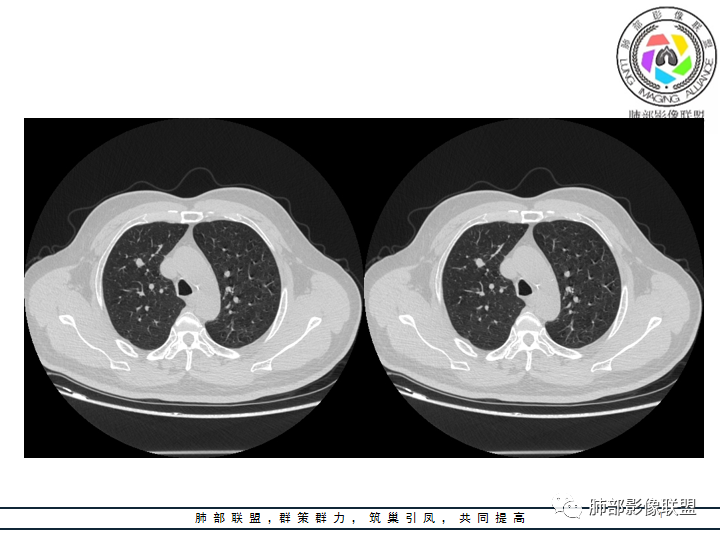

影像资料

老年男性患者,长期吸烟史,没有呼吸系统临床表现。胸部CT示右肺上叶实性密度结节影,密度均匀,未见空洞及钙化,边缘较光整,未见分叶及毛刺。血管影旁现侧出,支气管进入并截断,不均匀强化。

影像上结节影或块影一旦与支气管密切相关(如截断),不支持硬化性肺细胞瘤、错构瘤、孤立性纤维瘤等良性病灶。如此清晰的边缘也不符合一般意义上的炎性渗出。